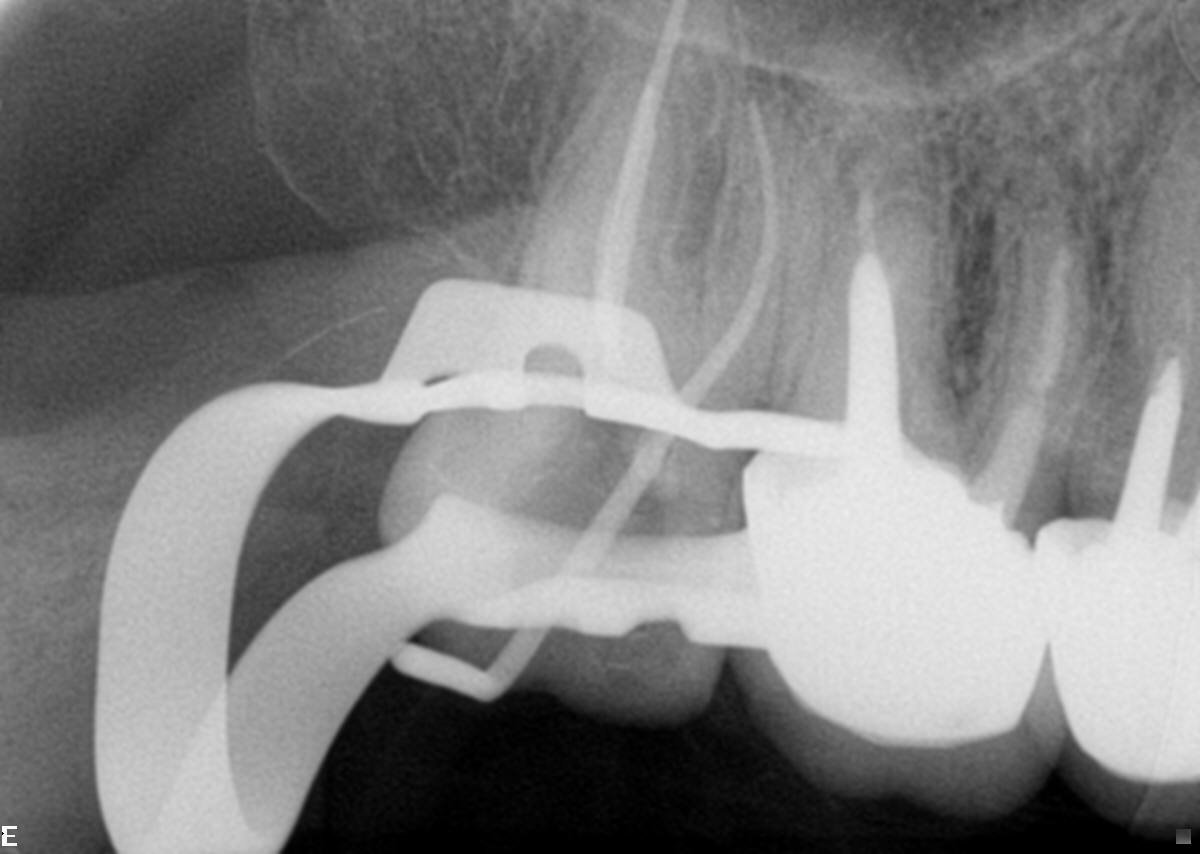

- Em seguida, relatou ter passado por um profissional que solicitou a ajuda de microscópio por não conseguir descer nos canais. Então, fizemos uma radiografia periapical onde constatou-se atresia em raiz distal, e atresia e curvatura em raiz mesial (Figura 3).

- Então, para a modelagem nos canais vestibulares, utilizou-se as limas 20.04 e 26/04 (Figura 4).

Figura 2 Figura 3 Figura 4 Figura 5 Figura 6 Figura 7